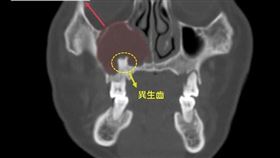

10年鼻血流不停!一查「牙齒」竟長進鼻腔

台中6旬婦人十年前開始出現擤鼻涕帶血絲及鼻涕倒流等狀...

鼻竇炎好不了還流膿 竟是鼻腔長牙齒

新竹40歲的小張長期右側鼻塞,原以為是因為自己在工廠...